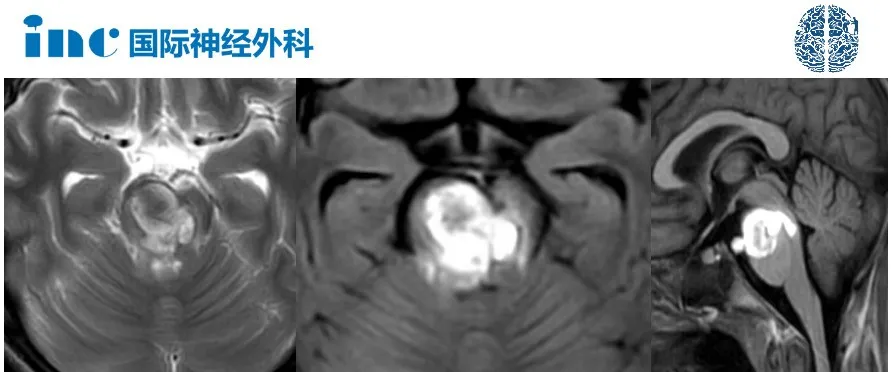

颅脑CT检查,小豪出现了严重的脑干出血伴水肿,海绵状血管瘤出血。

大的出血性病变位于桥脑腹侧靠上部位,并伴有周围内源性水肿。总之,这是一个相当严重和危险的病变,这一事实已经反映在之前的临床症状上了。